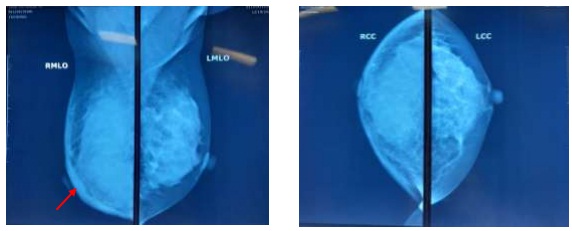

- X-quang tuyến vú: nhu mô đặc típ C, toàn bộ vú phải tăng đậm độ, mất cấu trúc ống tuyến, co kéo, dày da vú.

Hình 2. Phim X-quang tuyến vú (mũi tên đỏ chỉ tình trạng dày da vú)